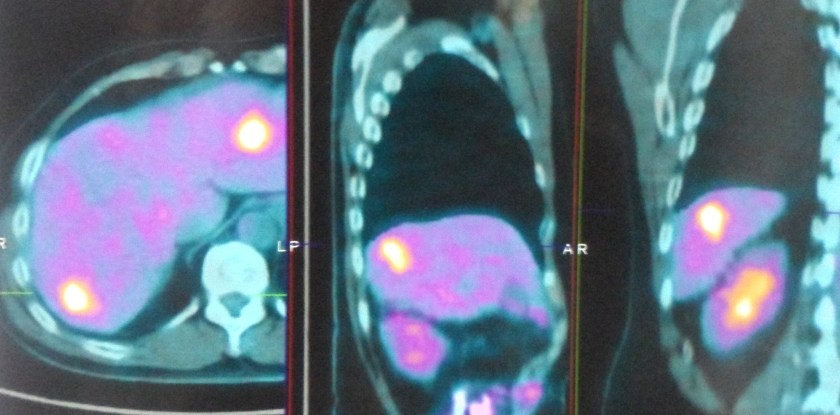

A PET scan showed:

- Two hypermetabolic metastatic nodules in the liver.

- No abnormal hypermetabolic foci or metastases elsewhere.